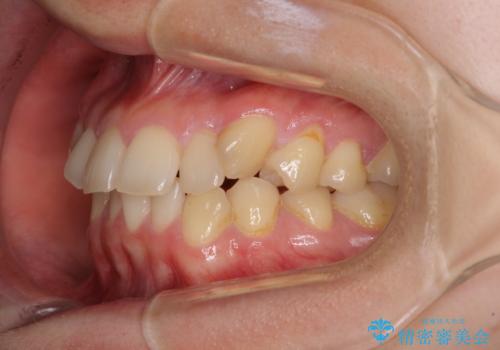

- 八重歯を気にして来院された患者様です。

診査を行ったところ、下顎前歯が1本欠損しており、下顎歯列が上顎よりも小さくなっていることで、上顎にデコボコが生じていました。

口元を見ると抜歯をして突出感を改善するような状態ではなかったため、上顎歯列のデコボコを整えて、歯列全体を後方に移動させることでバランスを取ることとしました。